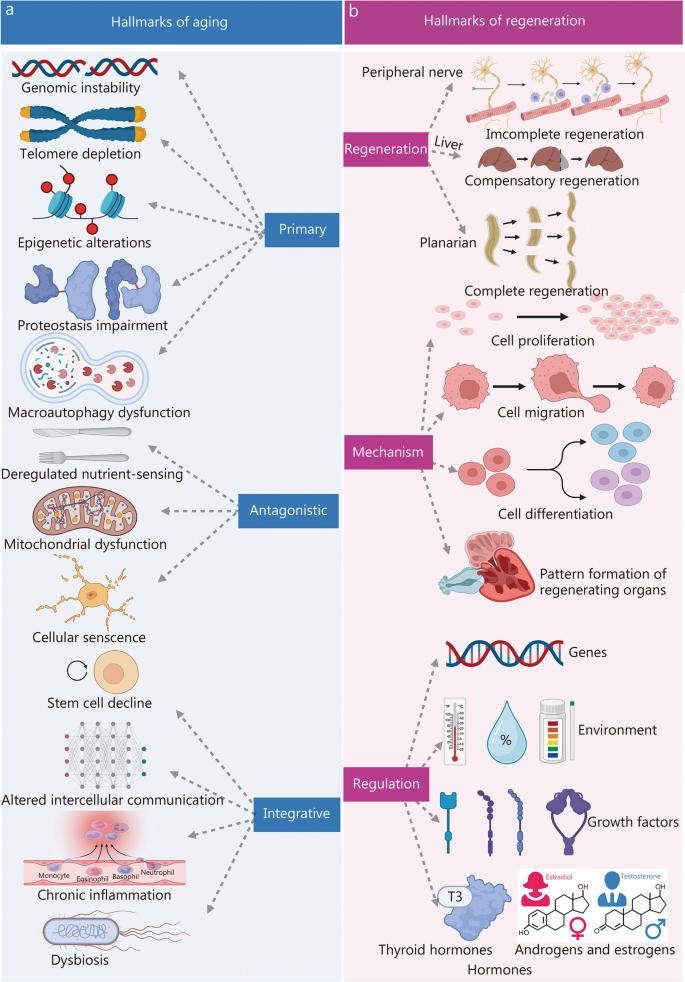

Aging is a progressive degenerative state that can be physiological and pathological [ 7 , 8 , 9 ] (Fig. 1 ). Physiological aging is observed in across many species, and is a degenerative process that occurs after maturation, including telomere attrition [ 10 , 11 ], DNA damage [ 12 , 13 ], mitochondrial dysfunction [ 14 , 15 ], loss of nicotinamide adenine dinucleotide (NAD + ) levels [ 16 , 17 ], impaired macro-autophagy [ 18 , 19 ], stem cell exhaustion, inflammation [ 20 , 21 ], loss of protein balance [ 22 ], deregulated nutrient-sensing [ 23 ], altered intercellular communication [ 24 , 25 , 26 ] and dysbiosis [ 27 , 28 ], thereby leading to systemic functional decline. Importantly, these changes are decentralised and interactive, not independent of each other. Pathological aging includes the senile pathological aging changes, which are caused by various external factors, such as cardiovascular disease [ 29 ], cerebrovascular disease [ 30 ], degenerative joint disease [ 31 , 32 ], diabetes [ 33 ], Parkinson’s disease [ 34 , 35 ], Alzheimer’s disease [ 36 ], cancer [ 37 , 38 , 39 ], and degeneration of multiple organ functions. These aging-induced cellular physiological and pathological changes can reflect the underlying nutrient sensing, intercellular communication, protein stabilisation, epigenetics, and molecular abnormalities in DNA damage repair, leading to genomic instability and damage. Further understanding of the different molecular mechanisms involved in the aging process is of great importance for preventing aging and prolonging the lifespan.

Aging drivers and age-related diseases. Major physiological features of aging include NAD + loss, telomeres attrition, mitochondrial dysfunction, stem cell exhaustion, disabled macro-autophagy, DNA damage, protein balance loss, inflammation, dysbiosis, deregulated nutrient sensing, and altered cellular communication. These physiological characteristics of aging are primitive, antagonistic, and integrated, and their interaction promotes aging. When aging reaches a certain threshold, organ and tissue function continues to deteriorate, which increases the incidence and mortality of aging-related diseases, including cardiovascular, cerebrovascular, degenerative joint disease, diabetes, Parkinson’s disease, Alzheimer’s disease, and cancer